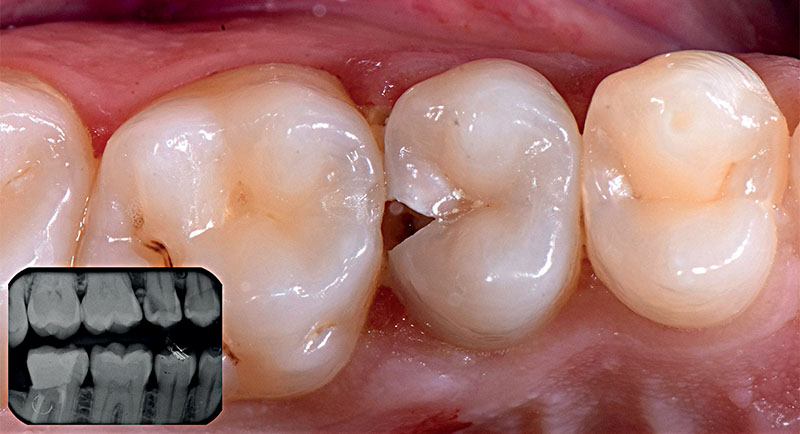

Fig. 01 : lésion carieuse sur la dent 25.

Un patient de 31 ans s’est présenté à la consultation avec une lésion carieuse sur la 25, ainsi qu’un tassement alimentaire entre 25 et 26.

• Carie dentinaire (ICD10 > K02.1) avec géométrie de classe II selon Black sur la dent 25

• Extension profonde de la carie sur la dent 25 jusqu’à la dentine (carie D4 selon Marthaler et Lutz)

• Fracture partielle de la 25 dans le secteur du bord distal